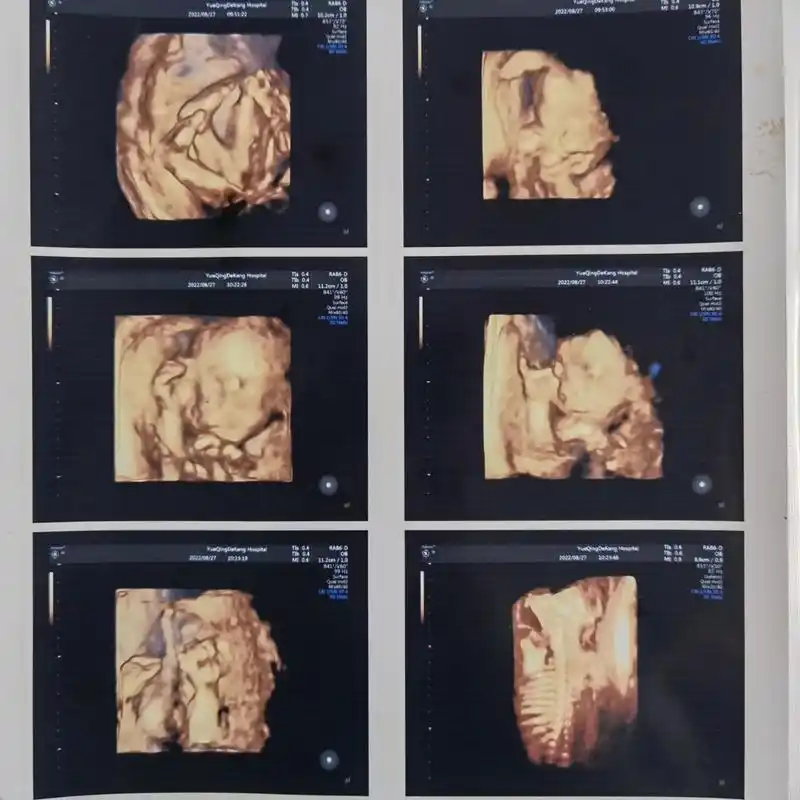

四维彩超照片 提前看见宝宝模样.

四维彩超的照片,准确率还是挺好高的,生下来基本一样,很秀起的小公主

四维彩超照不知不觉自己已经怀孕23周了四维也一次过还是蛮开心的